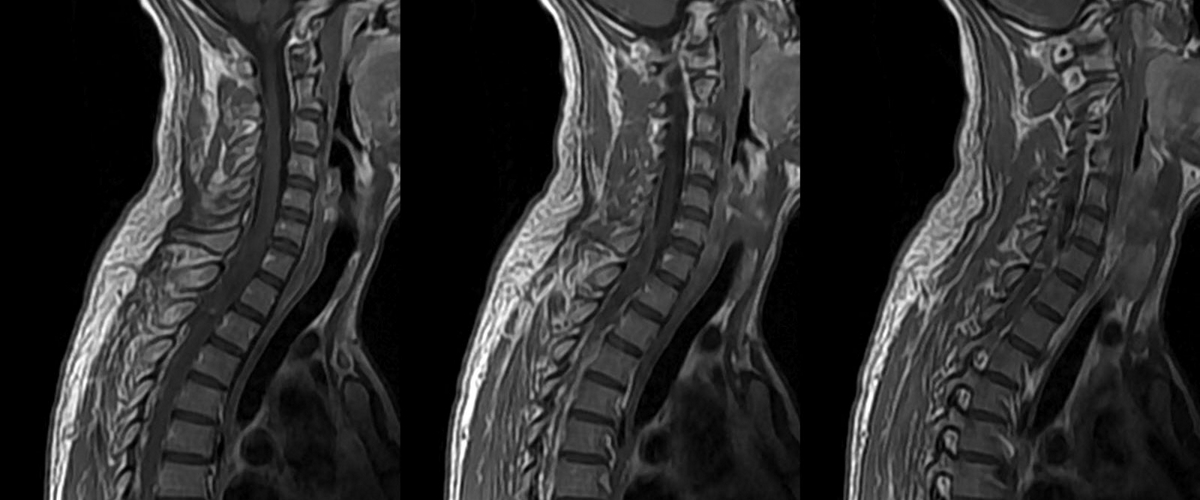

Как вернуть движение: технологии для восстановления после травм позвоночника

Представьте, что тонкая нить вашего спинного мозга — это скоростная магистраль, по которой мчатся электрические импульсы от мозга к мышцам. Серьёзная травма — и дорога разрушена. Связь потеряна. К сожалению, наше тело не умеет чинить такие сложные «провода». Но что, если мы построим умный мост в обход разрушения? Именно над этим сейчас бьются лучшие умы.